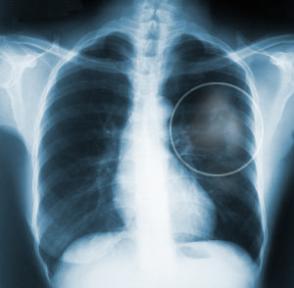

"Celem tego dnia i towarzyszącej mu kampanii jest przede wszystkim zmniejszenie narażenia na dym tytoniowy poprzez zachęcenie palaczy do rzucenia palenia oraz niepalenia w obecności osób niepalących. Warto rzucić palenie z uwagi na to, że każdy papieros kosztuje nas 11 minut życia. Po rzuceniu palenia poprawia nam się funkcjonowanie płuc, spada ryzyko zawału, a także powraca nam smak i węch."